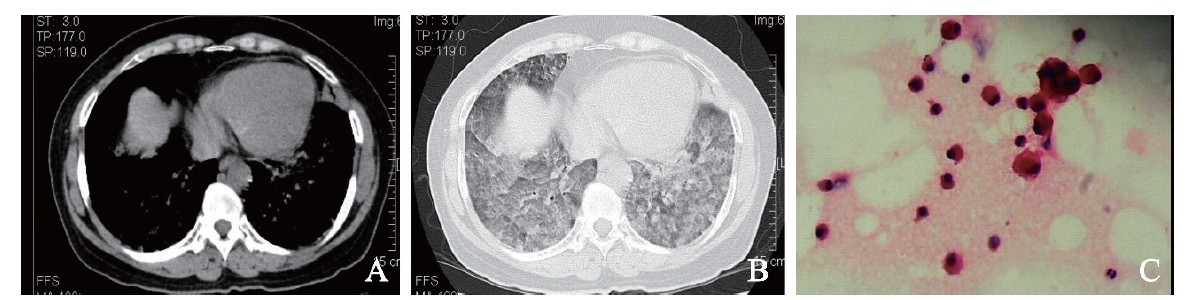

例4 患者男,39岁。因右侧胸背痛9 d于2018年7月9日收入我科。9 d前患者无明显诱因出现右侧持续性胸背痛,无胸闷、发热、心悸。当地医院予头孢呋辛联合左氧氟沙星抗感染及止痛治疗,7月7日当地医院胸部CT示右肺中下叶炎症,右侧胸膜增厚伴少量胸腔积液。起病以来,患者无皮疹、盗汗等,近1周体质量下降4 kg。既往史及个人史无特殊。入院体格检查:体温 37.1 ℃,脉搏 96次/分,呼吸 20次/分,血压125/85 mm Hg。双肺呼吸音粗,右下肺可闻及少许细湿啰音。入院后查血常规示:血红蛋白137 g/L,白细胞6.62×109/L, 血小板291×109/L,凝血酶原时间、活化部分凝血活酶时间、凝血酶时间、纤维蛋白原均正常,D二聚体正常。自身免疫相关指标:抗心磷脂抗体IgG(+),核周型-抗中性粒细胞胞浆抗体(+),抗核抗体颗粒型(+),抗双链DNA抗体(+)。入院后予哌拉西林钠-他唑巴坦钠4.5 g、每8 h 1次静脉滴注,未见明显好转。7月18日胸部CT示:①右下肺动脉及其分支栓塞;②右肺下叶炎性病变,部分较前吸收,部分范围较前增大(图4),建议继续治疗后复查;③右侧胸腔少量积液,较前吸收。右肺下叶见多发不规则片状影,边界欠清,增强扫描强化不明显(图4A、B)。7月12日BAL液基细胞学及涂片可见较多泡沫样组织细胞(图4C)。考虑SLE合并抗磷脂抗体综合征及肺栓塞,予甲泼尼龙40 mg、每日1次,羟氯喹0.2 g、每日2次,甲氨蝶呤10 mg、每周1次及利伐沙班10 mg、每日2次抗凝治疗,患者症状好转出院。至撰稿日长期门诊随访,治疗效果良好,未再出现胸痛等不适症状。

图4 例4 SLE合并抗磷脂抗体综合征及肺栓塞患者的胸部CT及BAL涂片结果

A:胸部CT纵隔窗;B:胸部CT肺窗;C:BAL涂片(HE染色,×400)